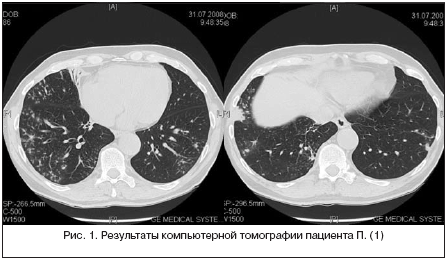

В паренхиме S1-S2 сегментов верхней доли правого легкого определяются гетерогенные интертисциальные изменения за счет полиморфных очагов, размером от 8,5 мм до 44,1 мм в поперечнике, на фоне которых визуализируются участки уплотнения по типу матового стекла

В других сегментах паренхима без очаговых патологических образований, нормальной пневматизации. Архитектоника легочного и сосудистого рисунка легких без особенностей. Просвет трахеи и главных бронхов свободен, стенки без патологических изменений. Легочные синусы свободные, без патологических изменений. Легочные синусы свободные, без патологических изменений. Плевральные листки не утолщены.

Повторное РКТ 9 января 2018г. дало тот же результат, единственная разница в размерах: в первом случае от 8,5мм до 44,1мм. В поперечнике, во втором случае от9,6 мм до 44.4 мм в поперечнике.